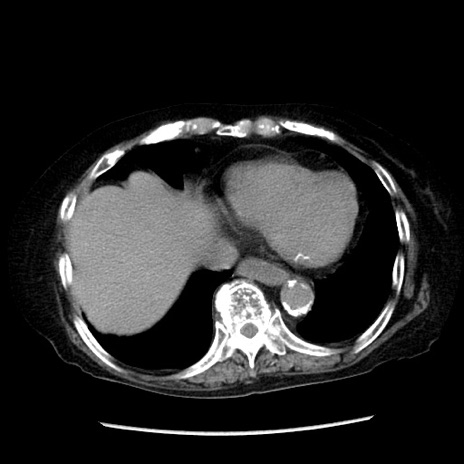

症例14(横断像)

【症例】 90歳代女性

【主訴】 腹痛・嘔吐

【現病歴】今朝から左側腹部痛を認めた。 経過観察していたが、嘔吐を認めたため来院。

【既往歴】 子宮癌術後

【身体所見】 意識清明、BP 127/54mmHg、P 98bpm Sp02 95%(RA)、BT 35.8°C、腹部平坦・軟腸ぜん動音聴取良好、右下腹部圧痛(+) 反跳痛なし

【データ】WBC 9800、CRP 0.46